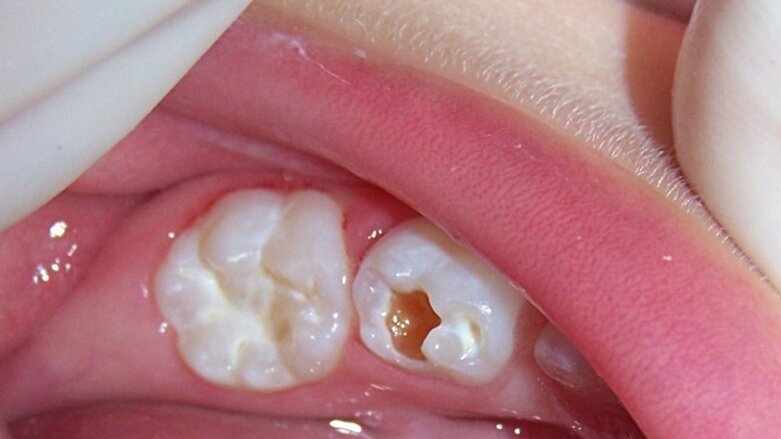

Figura 1. Paciente de 35 meses de edad con lesión de caries en dentina en el órgano dentario 74 (ICDAS 5) y lesión inicial de caries en el 75 (ICDAS 2).